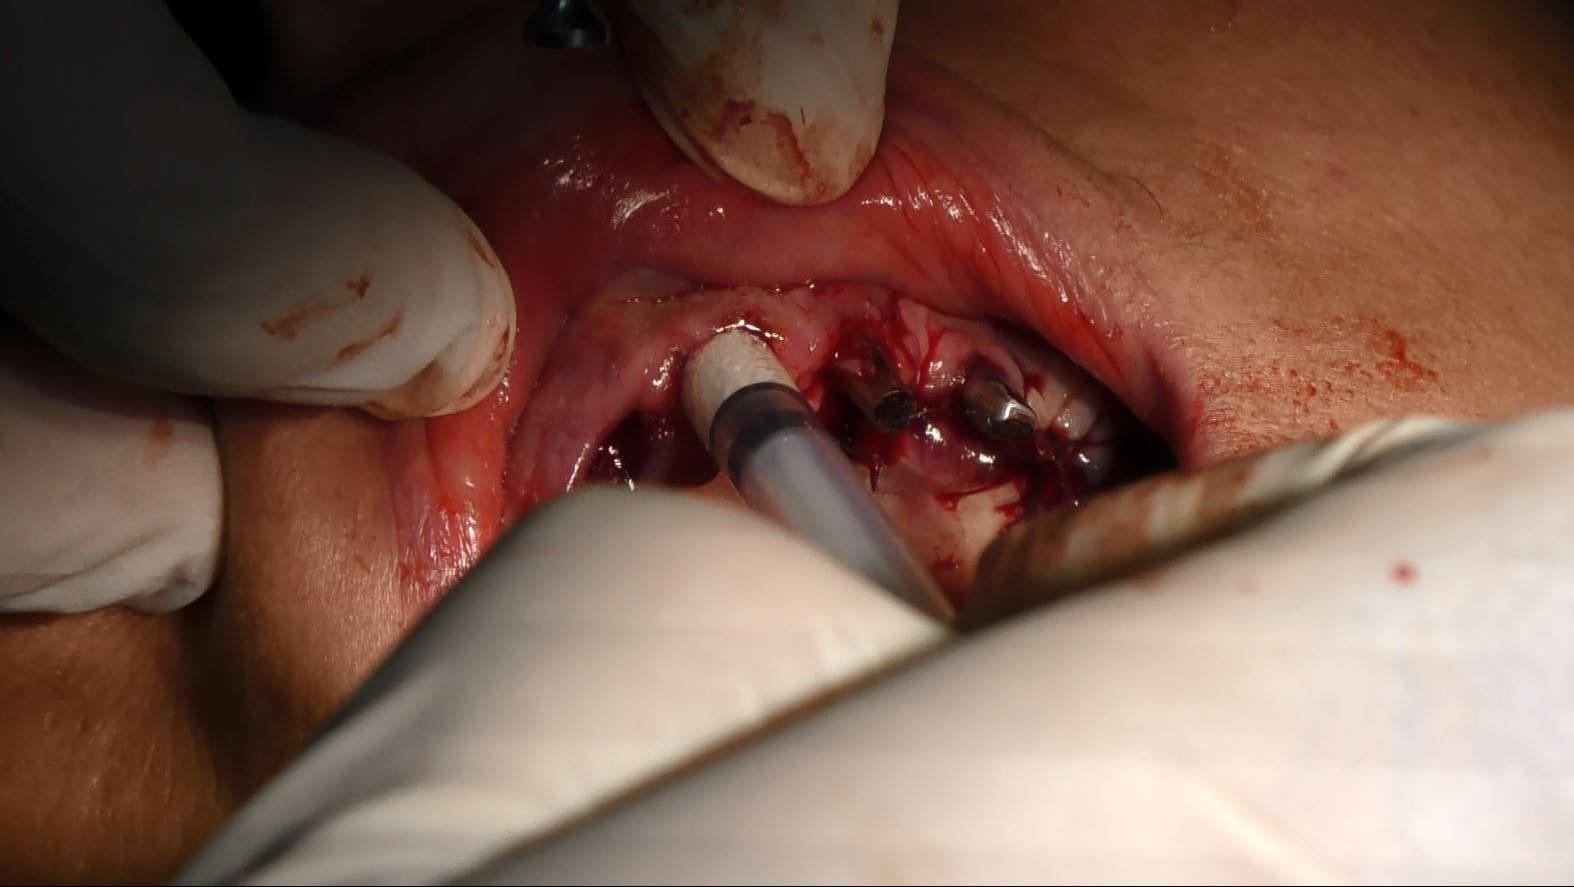

Preservazione dei Volumi durante le Estrazioni:

Nelle estrazioni dentali, riempiamo gli alveoli con materiale biocompatibile per preservare i volumi, specialmente nelle zone strategiche per l’estetica vicino al labbro superiore. Questa pratica è fondamentale per ottenere risultati altamente naturali, soprattutto nel contesto estetico femminile.